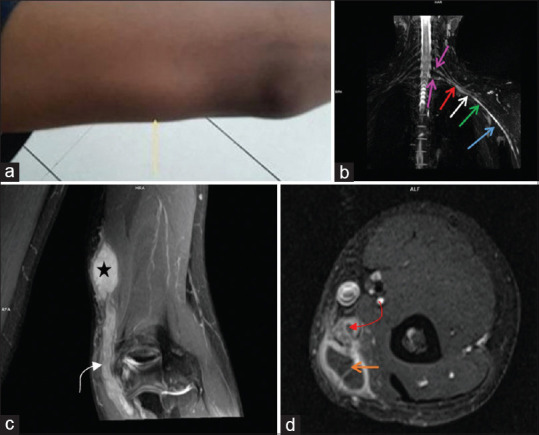

背景和目的:磁共振神经成像(MRN)允许神经的直接可视化,这可以有助于周围神经疾病的诊断、表征和定位。我们计划对转介行核磁共振的周围神经损伤患者进行研究,并将核磁共振结果与神经传导研究(NCS)对各种局灶性神经疾病的结果进行比较。方法:这项前瞻性研究进行了超过1年半,涉及58名临床诊断为局灶性周围神经病变的受试者,他们被转介到放射诊断和影像学部门进行MRN检查。MRN检测到的局灶性周围神经病变范围与NCS和/或肌电图结果以及手术和/或组织病理学结果相关并进行比较。采用χ 2检验和Fisher精确检验评价MRN与NCS结局的相关性。结果:该研究确定了广泛的周围神经病变。在58例受试者中,52例(89.6%)发现异常,而6例(10.3%)患者未显示任何明显异常。50例(86.3%)患者在MRN和NCS上均表现异常,5例(8.6%)患者在MRN和NCS上均未表现异常。2例(3.4%)MRN异常但NCS结果正常,1例(1.7%)MRN正常但NCS结果异常。在58例mri检查中,25例发现臂丛受累。结论:核磁共振成像是评价周围神经病变的一种高度敏感的工具。其与NCS和术中发现的相关性进一步支持了其临床应用。在周围神经病变的诊断过程中,3t核磁共振成像应被视为一种关键的成像方式。此外,它还可以作为规划治疗干预措施和评估各种患者亚群预后的有价值的指南。

Results: The study identified a broad spectrum of peripheral nerve pathologies. Out of 58 subjects, abnormalities were found in 52 (89.6%) subjects, whereas six patients (10.3%) did not show any significant abnormalities. Fifty patients (86.3%) showed abnormalities on both MRN and NCS, while five patients (8.6%) did not show any abnormalities on either MRN or NCS. Two patients (3.4%) showed abnormalities on MRN but had normal NCS results, and in one case (1.7%), MRN was normal but NCS showed an abnormality. Out of the 58 MRN examinations, 25 were found to have brachial plexus involvement.